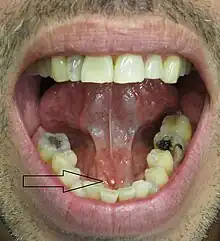

- Palpable hard lump, if the stone is located near the end of the duct.[1][3] If the stone is near the submandibular duct orifice, the lump may be felt under the tongue.

- Erythema (redness) of the floor of the mouth (infection).[3]